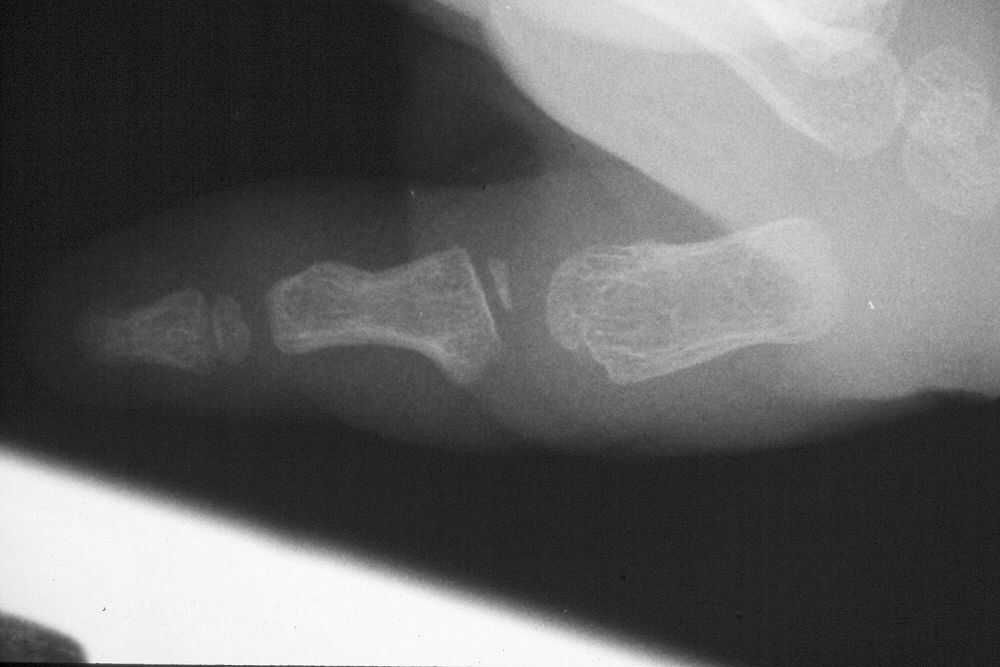

| Case 1. Wassell IV duplication of the proximal and distal phalanges, with characteristic deviation of the thumbs away from each other at the MCP and toward each other at the IP joints. This was corrected by metacarpal head narrowing, opposing closing wedge osteotomies of the metacarpal and proximal phalanx and collateral ligament reconstruction using parts from the deleted digit. |